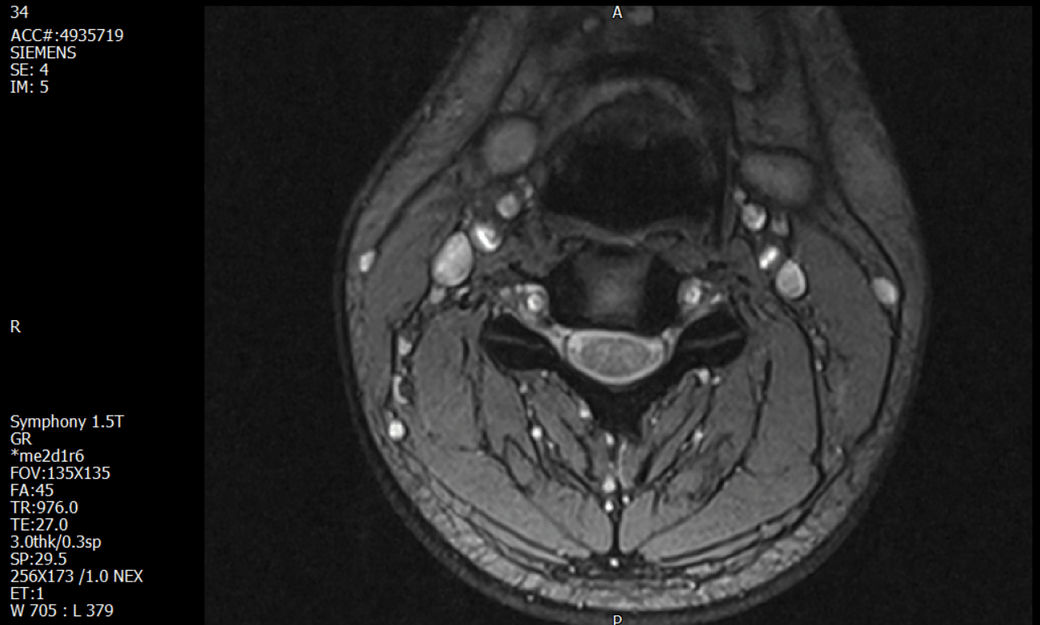

경추 요추 디스크 MRI판독 부탁드립니다.

- 3개월전 좌측 상지 저림(힘빠짐) 발생. 이틀뒤 에 좌측 하지 저림(힘빠짐) 발생.

(힘이 축처지는 느낌이라서 힘빠짐이라고 하지만, 실제 근력 문제, 감각이상, 활동 문제 없음)

-11월, 증상발생 직후 잠실소재 척추전문병원 MRI 요추경추 촬영 후 신경외과 박사 진료, 허리는 매우 건강, 경추는 퇴행성 진행되고 있지만 디스크라고 보기 어려움. 신경막만 살짝 건드리는 정도고 이 정도로 힘빠짐이나 저림이 오지 않고 원인은 다른 곳에 있을 가능성.

-12월, 분당서울대병원 재활의학과 진료, MRI 영상보고 딱히 다른 말은 없었음. 근전도 검사해보자 해서 신경전도, 근전도 검사 진행, 검사결과 이상없었고, 신경쪽 문제는 아예 배제해도 될것이라고 함. 정신쪽에 기인한 문제일 가능성 제시.

-올해 1월, 국립암센터 재활의학과 진료, 병명을 찾기가 쉽지 않을 것

-올해 1월, 분당서울대병원 신경과 진료, MRI영상보더니 디스크가 있고 저림과 힘빠짐이 이에 기인했을 가능성이 충분히 있다고함. (경추만 말한것인지 요추도 포함인지 모르겠으나 디스크 시술 방안을 제시함) , 팔다리가 우연이 동시에 저림이 올수 있는지에 대해서 물었더니 이틀 상간으로 발생했기 때문에 동시라고 보기 어렵다고함...

1. MRI 상 , 경추와 요추에 디스크가 있나요? 있다면 좌측 팔과 다리에 저림 및 힘빠짐을 줄 정도인가요?

• 1. MRI 사진을 보았을 때 디스크를 의심해볼 수 있는 소견이 살짝살짝 보이긴 합니다만, 상하지의 저림 및 힘빠짐을 유발할 정도인지는 솔직히 회의적입니다.

2. 영상의 퀄리티는 나쁘지 않아 보입니다. 굳이 재촬영을 하실 필요는 없어 보입니다.

3. 개인적으로는 디스크로 인한 증상이 아닐 것으로 보나, 만약 디스크가 맞다면 우연하게 목과 허리 디스크 발병이 이틀 간격을 두고 나타났을 가능성을 생각해야 하는데, 현실적으로 그 가능성이 높지 않습니다.

4. 말씀하신 것처럼 특히 요추부 MRI는 디스크를 찾기 어렵습니다.

상기 MRI 소견으로는 심한 증상을 보일 정도는 아니며 디스크의 가능성은 적어보입니다.